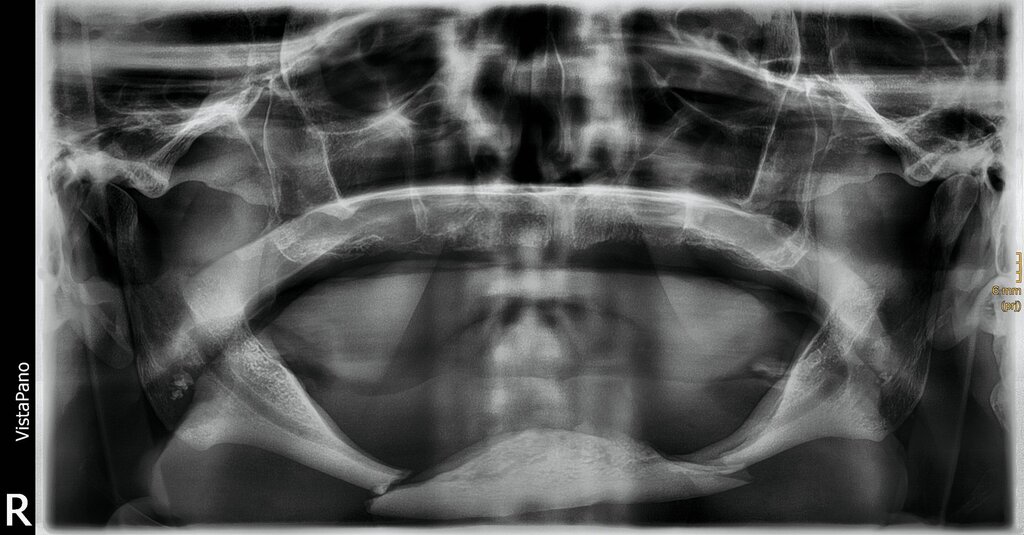

Durch den Rettungsdienst wurde dem Universitätsklinikum Freiburg ein 75-jähriger Patient zugewiesen. Er war aus etwa einem Meter Höhe von einer Leiter gestürzt. In der Notfalldiagnostik mittels Computertomografie (CT; Polytraumaspirale) wurden eine komplexe doppelte Unterkieferkorpusfraktur bei atrophem Unterkiefer (Pencil bone fracture) sowie eine Beckenringfraktur vom Typ Tile B diagnostiziert.

Während die Klinik für Orthopädie und Unfallchirurgie ein konservatives Versorgungsregime mit 20 kg Teilbelastung über sechs Wochen zur Behandlung der Beckenringfraktur empfahl, planten wir in der MKG-Chirurgie die operative Frakturversorgung des stark atrophierten und disloziert frakturierten Unterkiefers. Der während der Notfalldiagnostik erstellte CT-Datensatz wurde auf eine Voxelsize von 0,6 Millimetern zurückgerechnet und in einem dafür entworfenen und zertifizierten Forum eines externen Unternehmens zur weiteren Bearbeitung hochgeladen.